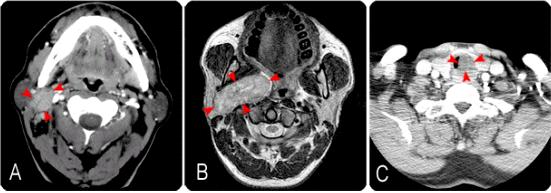

[ 침샘종양의 영상검사소견 ]

[사진설명] 다양한 양상으로 나타나는 침샘종양, (A) 우측이하선 심엽에 발생한 침샘암, (B) 우측 부인강에 발생한 거대한 양성 침샘종양, (C) 기도에 발생하여 호흡곤란을 일으킨 침샘암 (소타액선암)